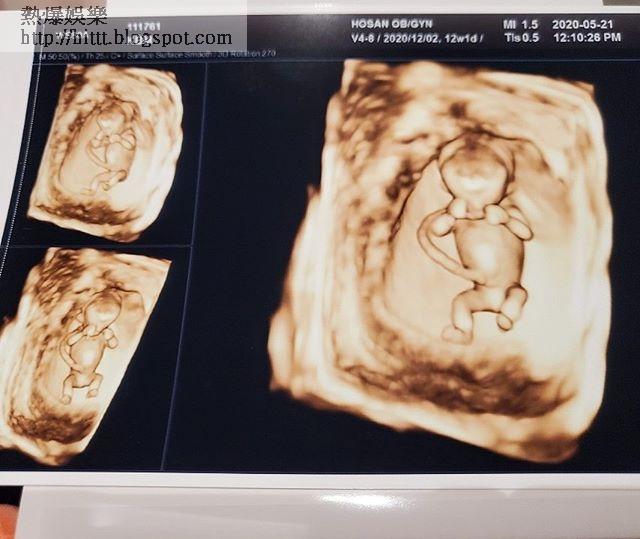

不少網民都指金甫美奉子成婚才急急在疫情之下結婚,又指奉子成婚不是值得宣揚的事情。而金甫美前日更於IG公開超聲波圖片,大晒腹中胎兒的情況,懶理受批評。不過有韓媒見金甫美成為新聞人物,即重點報道她的出道過程,又暗示她出道時演技差。